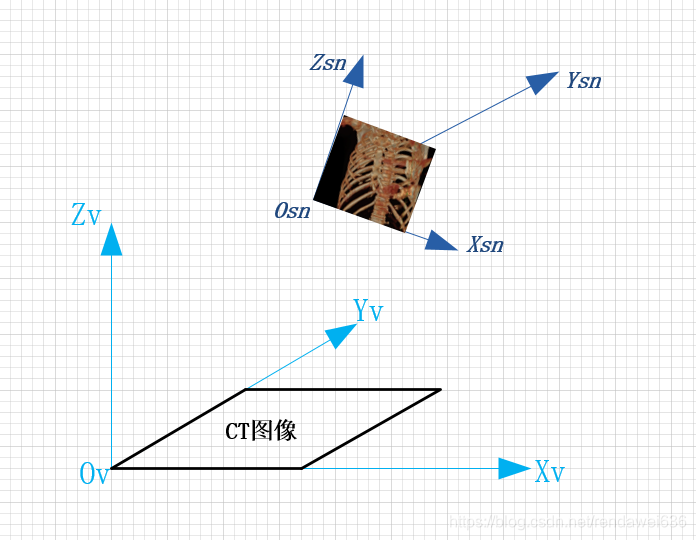

内窥图像生成的过程,是在观测点Osn沿着Ysn的方向进行平行光照射,对光线上经过体素进行渲染,渲染得到的结果图像就是内窥镜图像。本文,不讨论光照模型,只关注坐标的变换。所以,关键点就是求Osn到Ov的转换矩阵,进而计算在Osn中的坐标,映射到在坐标系Ov中的实际体素坐标。

以上的是一个直观的问题描述,在实际渲染算法引擎中,坐标系Osn到坐标Ov之间的变换,是通过一系列的变换的集合,下图就描述了,我们坐标系的定义,其中,比较关键的坐标系是:(坐标系都符合右手螺旋法则)

Ov:原始体素坐标系。坐标方向是Dicom中规定的坐标方向,以图像的左上角为圆心,图像左向右方向是x轴方向,从上到下是y轴方向,z方向是按照右手法则确定,坐标单位是毫米mm。

Osn:内窥镜坐标系。将体素坐标投射到XsnYsn平面上,就是内窥镜的最终的渲染图像。